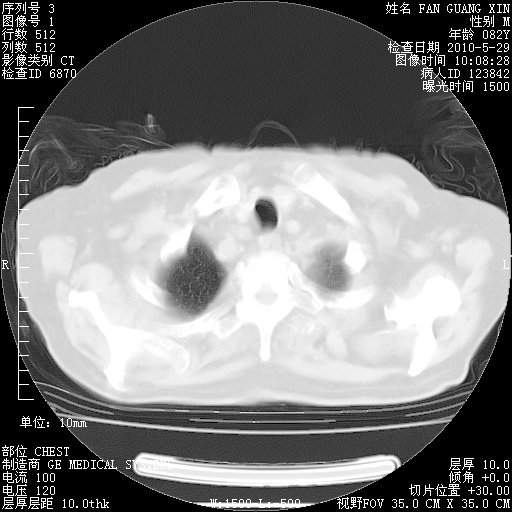

再治疗10天后的肺部CT

再治疗10天后的肺部CT 纵膈窗

阅读此次胸部CT,肺间质渗出性改变较入院时有吸收。目前从体温、白细胞、中性分叶明显增高,肯定存在细菌感染(发生医院感染哦,若无消化道及泌尿系统等感染的依据,肺部感染可能大)。若你院头孢哌酮舒巴坦钠耐药率较高,同意你的方案,若48小时体温仍高,可考虑使用碳青霉稀类抗菌药物,同时可予超声雾化、注意滴数时加大液体量。白蛋白33.30g/L较低哦,需加强营养等支持治疗。